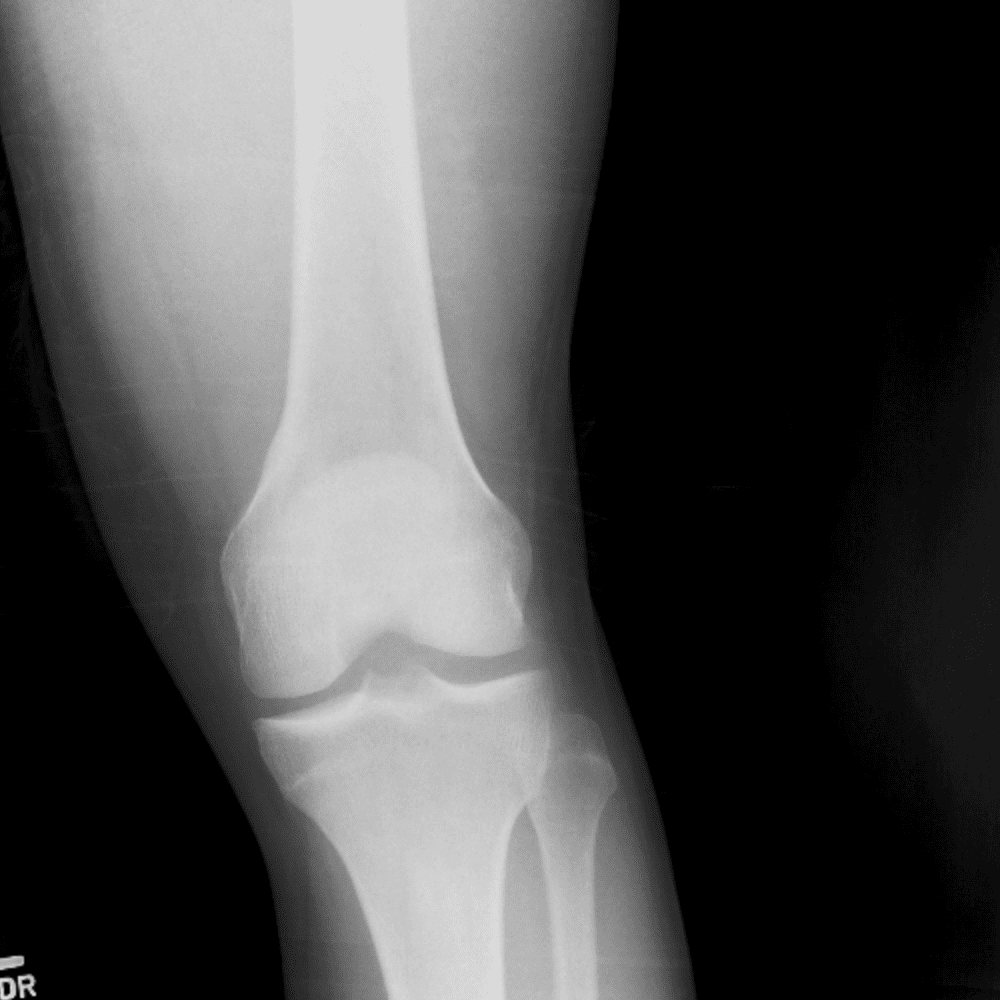

Simula o plantão incluindo casos sutis ou difíceis e alguns normais.